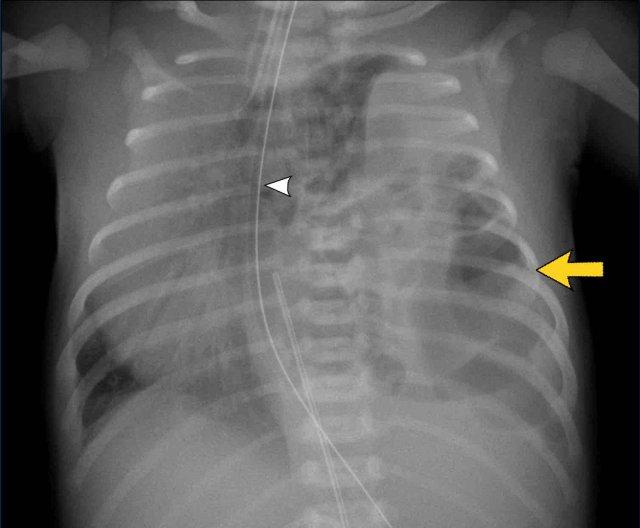

Hình ảnh

Trẻ sơ sinh đủ tháng với triệu chứng khó thở.

Mờ một phần vùng phổi trên bên trái.

Các quai ruột được nhìn thấy trong lồng ngực trái (mũi tên).

Sự dịch chuyển của các cấu trúc đường giữa được thể hiện qua sự lệch của ống thông dạ dày (đầu mũi tên)

Siêu âm cho thấy nhu động ruột trong các cấu trúc chứa khí và dịch, xác nhận thoát vị cơ hoành lớn.

Những hình ảnh này là của một trẻ sơ sinh đủ tháng với

khó thở.

Mờ một phần vùng nửa ngực trên bên trái.

Các quai ruột được nhìn thấy trong nửa lồng ngực bên trái.

Sự dịch chuyển của các cấu trúc đường giữa được thể hiện qua sự lệch của ống thông dạ dày qua mũi

(đầu mũi tên).

Phim ngực tư thế nghiêng cũng cho thấy các quai ruột trong lồng ngực.